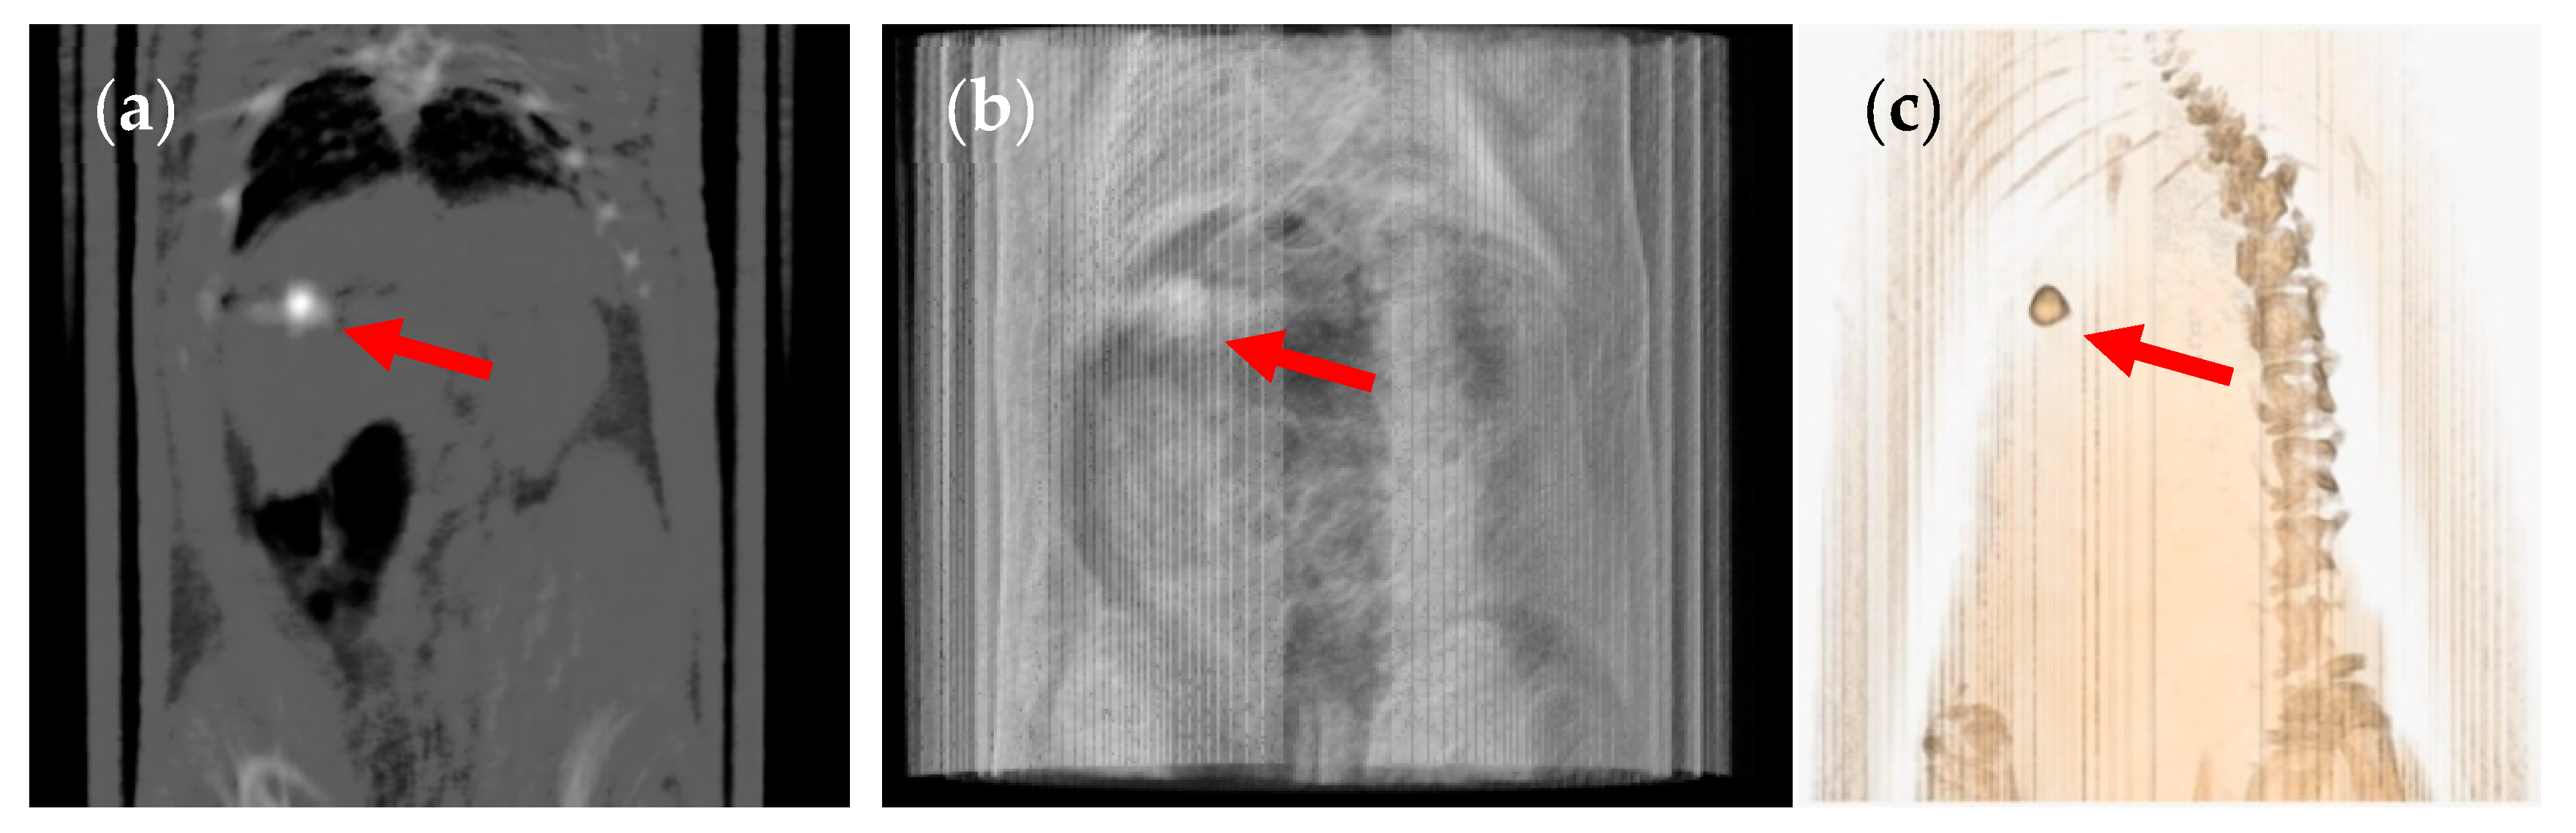

3. Results and Discussion